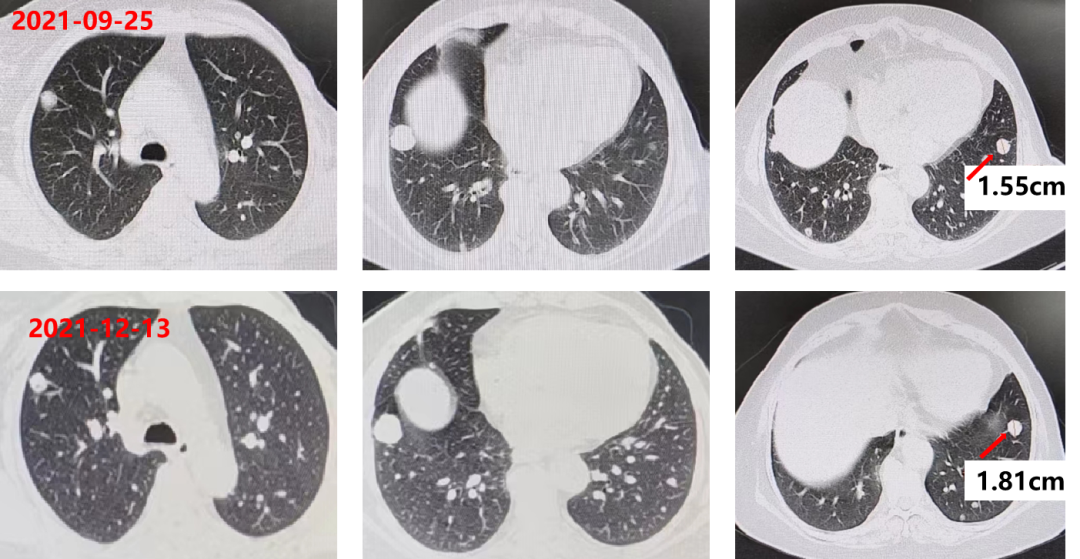

胸腹部增强CT:双肺多发转移瘤,较前片相比增大(较大者位于右肺下叶,长径约3.4cm,靶病灶增大,出现新病灶),直肠壁和肝左叶病灶未见变化。

疗效评估PD。

2022-06-07 复查 CEA:266.3ng/ml。

胸腹部增强CT:双肺多发转移瘤,较前片相比变化不大(较大者位于右肺下叶,长径约3.3cm,靶病灶与非靶病灶未见明显变化)。

疗效评估SD。